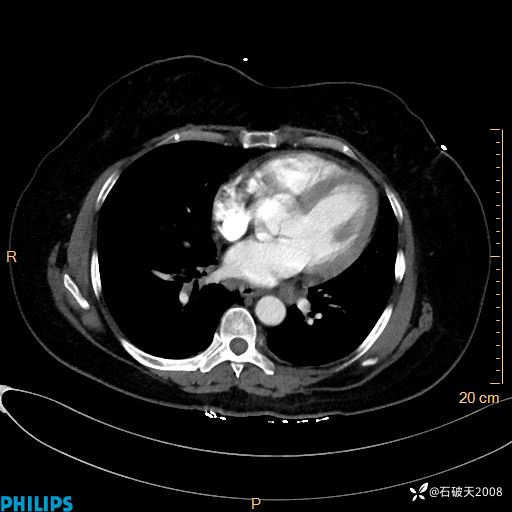

肺窗

纵隔窗